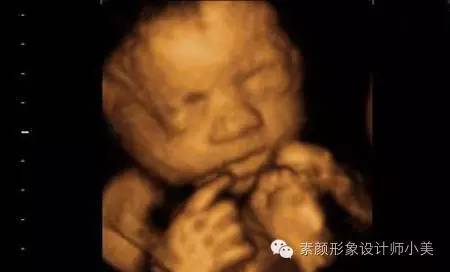

胎儿发育:

现在胎儿开始频繁地胎动了,身长已经接近14厘米,体重大约200克。这时候是您和宝宝交流的大好机会,宝宝在您的肚子里面可什么都知道,您只要和他/她说话,他就会做出相应的反应。如果是女孩,她的阴道,子宫,输卵管都已经各就各位;如果是男孩,宝宝的生殖器已经清晰可见。